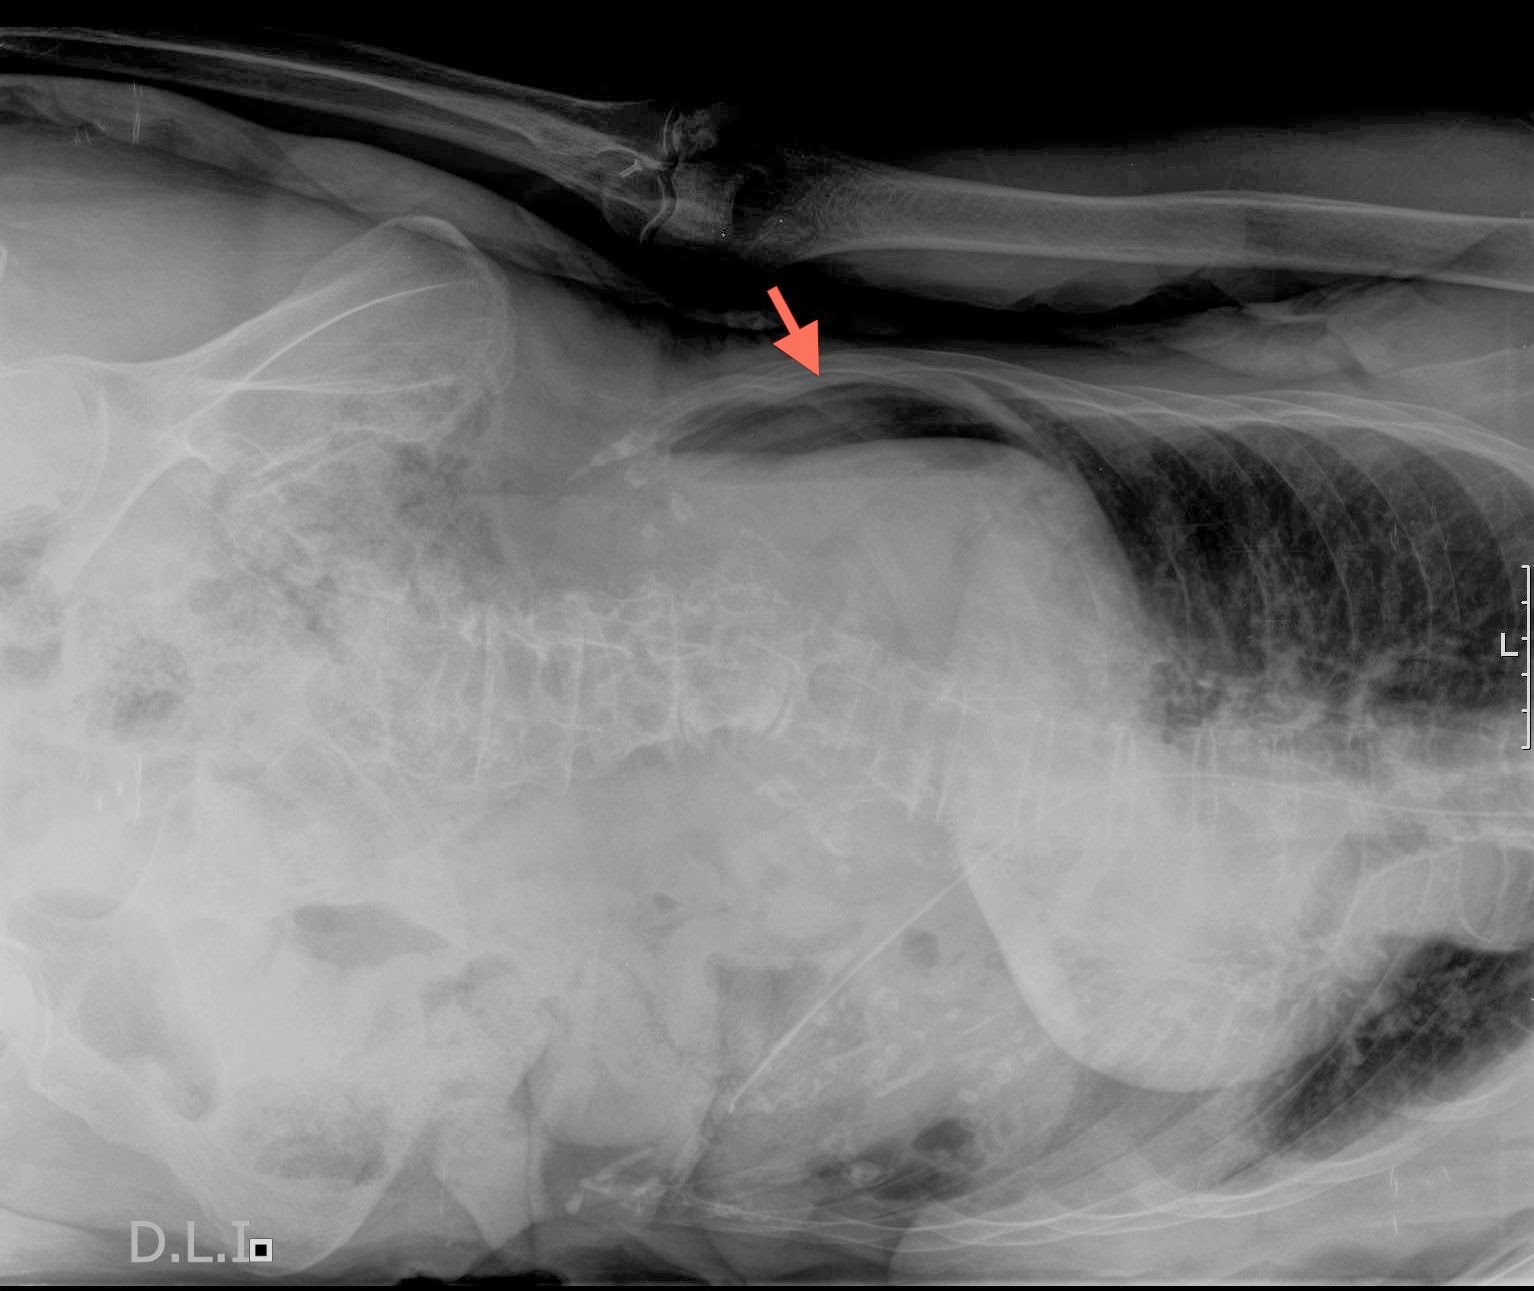

Patrn areo intestinal: El aire dentro de las asas intestinales se identifica por presentar unas lneas. Examen radiologico abdominal en urgencias INDICACIONES PARA REALIZACION DE UNA RADIOGRAFIA ABDOMINAL. Esto se llama aire libre y es signo de una ruptura. Si se originan en la pared intestinal, se trata de divertculos intestinales.

Despus del examen, cuando el aire salga del colon. - Aparato Digestivo El aire que pasa al intestino delgado o se absorbe, o pasa al intestino grueso. Est originado en estructuras de la pared abdominal. Es una condicin patolgica definida como la infiltracin de aire dentro de la pared del tracto gastrointestinal. Epigstrica y niveles de lquido y aire en la radiografa abdominal.

La presencia de gas en la pared intestinal o en la vena porta, es un. Revista chilena de ciruga - Neumatosis Intestinal: Caso Clnico. Descubren que la distensin abdominal puede evitarse con la. Introduccin La neumatosis intestinal es el resultado de la infiltracin de aire en la pared del intestino.

CIRUGIA DE LA PARED ABDOMINAL Ctedra de ciruga. Alteraciones de la pared intestinal como el aire intramural observado en la. Enterocolitis necrosante - , la enciclopedia libre Enterocolitis necrosante o necrotizante (ECN) es una enfermedad que aparece en recin. Semiologa del aparato digestivo En efecto, en ella podremos ver un nivel mediastnico aire-lquido que nos.